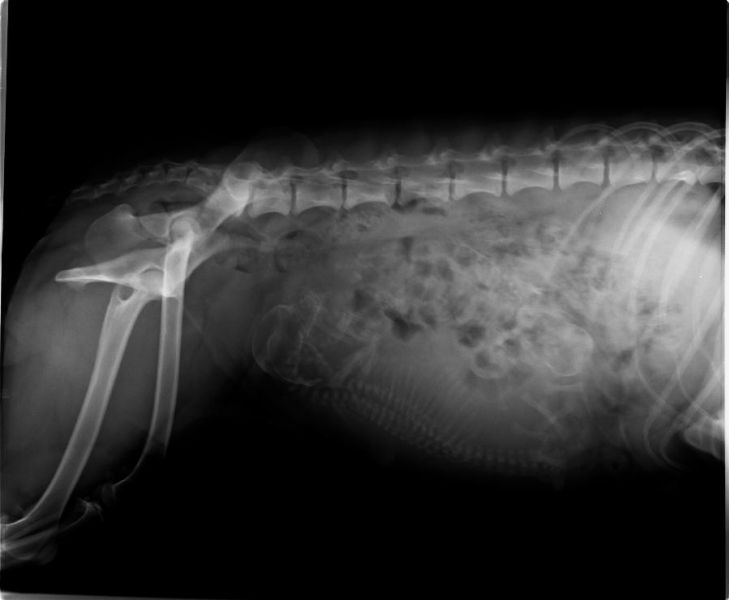

30 Trächtigkeitstag: Heute waren wir zum Ultraschal.

Der Arzt hat drei kleine Fruchtkammern gesehen.

Faith und Spell werden Eltern :grinning: